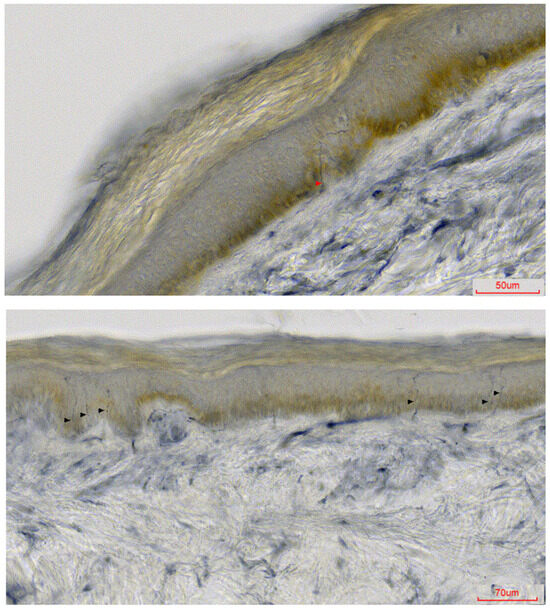

| CR | W 57 y | 46 y | Burning pain, shock-like sensations, NRS 8. | Mainly distal, occasionally proximal | No motor symptoms and signs | RLS | Interm | Abnormal * | Paracetamol, clonazepam—partial improvement | Sporadic | Trp101ter c.302G>A |